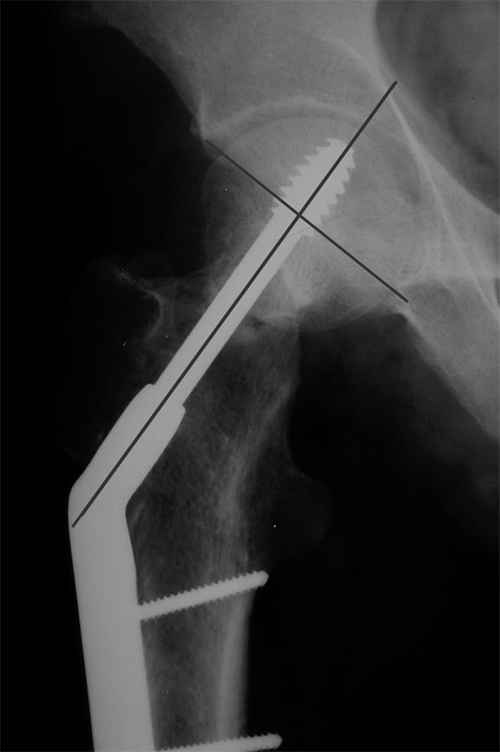

Больной Т. 1966 г.р.Травма 28.06.2007. Прооперирован в г. Бишкек, Оп:

Остеосинтез правого бедра системой DHS. В последующем беспокоили

периодические боли в правом тазобедренном суставе с иррадиацией в

коленный сустав в область передней поверхности правого бедра. Лечился

амбулаторно с незначительным эффектом.

В 07.04.2008 по 08.05.2008 года лечился в госпитале ГУВД и СО в

стационаре с Срастающийся перелом шейки правого бедра в условиях

фиксации системой DHS – боли уменьшились.Боли обострились 03.02.2009

внезапно, госпитализирован.

Результат - Псевдоартроз шейки правого бедра (имеются косвенные

признаки разрушения спонгиозной части головки бедра)Планируется -

Работоспособный возраст (43 года).Наиболее приемлемым и реальным

методом лечения предполагается: Удаление конструкций из бедра.

Заполнение полости от винта монолитным аутотрансплантатом из крыла

(крылев) подвздошной кости. Медиализация большого вертела.

Предполагаемый период нетрудоспособности 3-4 мес.